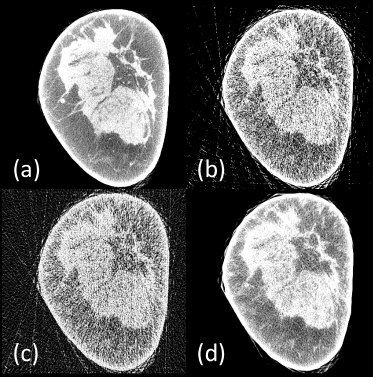

Refer to caption

Figure 4: Representative slices reconstructed using different methods. (a) The ground-truth, (b) FDK reconstruction from 75-view cone-beam projections, (c) FBP from 150 simulated parallel-beam projections, (d) DEER-BP, (e) DEER-NoWGAN, (f) DEER-FBP, (g) DEER-Sino, and (h) DEER. The red boxes mark the Regions of Interest (ROIs). Yellow circles mark some subtle details in the ROIs. Note that the final reconstructions were post-processed to remove irrelevant structures outside the field of view.

To demonstrate the effectiveness of the proposed method, three additional networks were trained and compared with the DEER network. In the first network, few-view images reconstructed by the FDK algorithm are eliminated from the DEER network, and the 150-view parallel-beam projections become the only input to the network. In the second network, few-view images reconstructed by the FDK algorithm are used as the only input to the network, and the back-projection part of the generator network G𝐺G is eliminated. Lastly, another DEER network without the WGAN component is trained and included for comparison to demonstrate the effectiveness of the WGAN framework in this task. The first network is denoted as DEER-Sino, the second network is denoted as DEER-FBP, and the third network is denoted as DEER-NoWGAN. Note that in the DEER network, the dimensionality of the input to the refinement portion of the generator network G𝐺G is Nb×1024×1024×2subscript𝑁𝑏102410242N_{b}\times 1024\times 1024\times 2. For a fair comparison, two copies of the input image were concatenated as the input to the DEER-Sino and DEER-FBP networks (i.e., in DEER-Sino, two copies of the image reconstructed by the back-projection part are concatenated as the input to the refinement part of the network; in DEER-FBP, two copies of the image reconstructed by the FDK algorithm are concatenated as the input to the refinement part of the network). The parameters and hyperparameters were fine-tuned for all three networks. In DEER-Sino, λal=0.002subscript𝜆al0.002\lambda_{\mathrm{al}}=0.002, and λsl=0.65subscript𝜆sl0.65\lambda_{\mathrm{sl}}=0.65. In DEER-FBP, λal=0.0025subscript𝜆al0.0025\lambda_{\mathrm{al}}=0.0025, and λsl=0.65subscript𝜆sl0.65\lambda_{\mathrm{sl}}=0.65. In DEER-NoWGAN, λsl=0.8subscript𝜆sl0.8\lambda_{\mathrm{sl}}=0.8.

As presented in Fig. 4, a representative slice is selected to visualize the performance of different methods. The image reconstructed from simulated 150-view parallel-beam projections using FBP, and the output from the back-projection portion in DEER are also included for comparison, which are denoted as FBP and DEER-BP respectively. Corresponding quantitative measurements are shown in Table II. Note that the image quality is well indicated by the three white features in the yellow circle in the zoomed-in areas of Fig. 4. Clearly, relatively simple post-processing methods tend to smooth-out or ignore these subtle but crucial details in the reconstructed images. However, a network-based reconstruction algorithm is better at recovering these details buried in the few-view artifacts. Although DEER-Sino has worse quantitative measurements than that of DEER-FBP, it accurately recovers these subtle features, which is desirable for clinical studies. It should be noted that the quality of the input to the DEER-Sino network is much lower than that of the DEER-FBP. Lastly, while results reconstructed by DEER-NoWGAN and DEER have similar quantitative values, certain features in images produced by DEER-NoWGAN appear to be dimmer than expected (e.g., the white feature at the bottom of the yellow circle in Fig. 4).

In few-view cases, analytical reconstruction methods such as FBP and FDK cannot produce high-quality results. The reconstructed results from post-processing image-based method, DEER-FBP, presented in Fig. 4 (f), cannot separate true features and artifacts. The main intuition of DEER is to learn a network-based reconstruction algorithm and to address the disadvantages of analytical reconstruction methods. As shown in the ROI of Fig. 4 (d) and Fig. 5, the proposed network-based reconstruction method helps reduce the amplitude of noise, compared with the FBP result presented in Fig. 4 (c). Then, the real features are more visible to the network. Note that as shown in Fig. 4 (d) and Fig. 5, DEER-BP appears to be less sensitive to the breast boundaries, resulting in darker boundaries compared with the image reconstructed by analytical FBP method. However, DEER-BP is an intermediate output from the proposed method, and the issue can be effectively addressed by the refinement portion of the network. As presented in Fig. 4 (g), the DEER-Sino network, in which the input is only the projection data, does not produce images with dark boundaries. Lastly, compared with FBPConvNet, residual-CNN, and DEER-NoWGAN, the WGAN framework was implemented in DEER for better recovery of subtle details and structural features but may result in a cost of compromising the quantitative measurements such as SSIM, and PSNR [5].

Figure 5: Absolute noise maps generated from images reconstructed by different methods, referenced to the ground-truth image. (a) FBP from 150-view simulated data, (b) DEER-BP.

It is clearly shown in Fig. 4 that the back-projection portion can learn a network-based reconstruction that is similar to the classic FBP method. The learned FBP allows the refinement part to recover some subtle features lost in image-domain networks. As presented in Fig. 5, the learned back-projection produces images with overall lower noise contents than the counterparts reconstructed by FBP, and removes most of the streak artifacts outside the FOV.